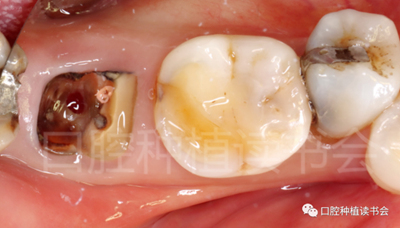

5.3.2 逐級(jí)預(yù)備種植窩洞后,側(cè)切鉆分根,微創(chuàng)拔除殘根,探查頰、舌側(cè)骨板完整,仔細(xì)搔刮拔牙窩,生理鹽水沖洗(圖15)。

圖15 微創(chuàng)拔牙后確認(rèn)種植窩洞位于牙槽間隔內(nèi)。

5.3.3 根據(jù)拔牙窩內(nèi)的牙槽間隔高度,植入康盛CANSUN柱形親水種植體(4.3*8mm),確保種植體肩臺(tái)與牙槽間隔平齊,種植體的所有表面均被自體骨包繞(圖16),植入扭矩為25N.cm。

圖16 盡量讓種植體表面被牙槽間隔的自體骨包繞。